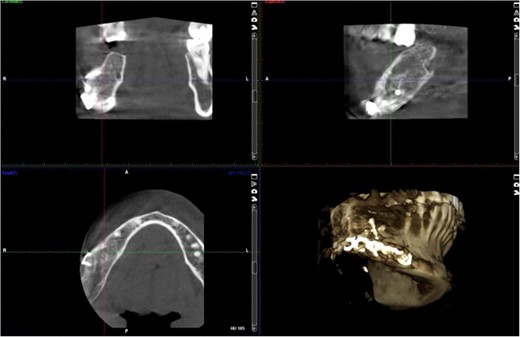

A 40-year-old woman presented with swelling on the right side of her mandible. She had completed orthodontic treatment 2 years earlier. A panoramic radiograph showed a unilocular radiolucency extending from the mandibular angle to the right first molar region (Figs 1–3).

The excised specimen’s histopathology confirmed its benign nature. One year postoperatively, the patient showed no infection or inflammation, with optimal mouth opening and mandibular movement. The reconstruction plate remained stable and intact (Figs 6 and 7).

Radiographic evidence showed expansile lytic lesions with sclerotic borders, consistent with IOS presentations [16]. Histology revealed Antoni A and B patterns, hyalinized Verocay bodies, and S-100 protein-positive cells, corroborating previous findings [17, 18].